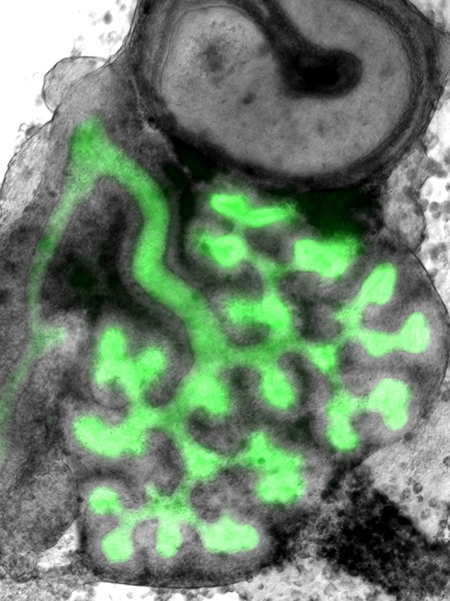

The mammalian kidney arises from intermediate mesoderm-derived tissue, namely the ureteric bud and the metanephric mesenchyme, which consists of nephrogenic and stromal precursor cells. Reciprocal inductive interactions between ureteric and nephrogenic cells induce formation of the ureteric-derived collecting system via a process termed renal branching morphogenesis and formation of nephrons. These interactions are modified by cell-cell communications between these elements and stromal cells. A fully functional kidney requires formation of a critical number of nephrons that drain urinary filtrate into the collecting system and ureter towards the bladder.

- Control of branching morphogenesis by integrin-linked kinase